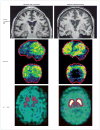

Figures